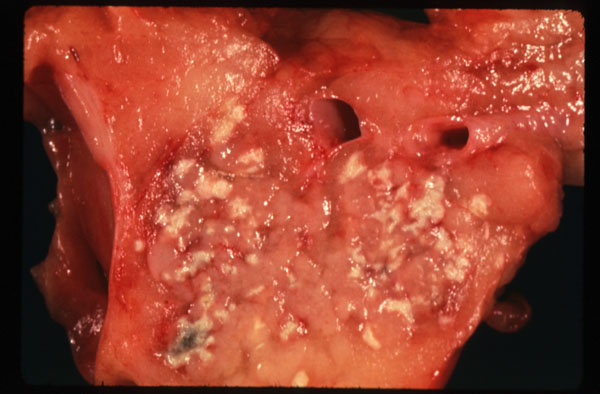

Fat necrosis of pancreas

The pancreas contains numerous whitish yellow specks corresponding to foci of fat necrosis induced by enzymatic digestion. Foci of fat necrosis undergo saponification.